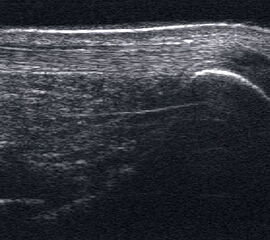

Achillessehne

Achillessehnenrupturen

Lagerung: Bauchlage, ggf. Sprunggelenk mittels Rolle unterlagert.

Schnittführung: LS über der Achillessehne, ggf. in leichter manueller Vorspannung der Achillessehne, damit diese parallel zum Schallkopf optimal eingestelt werden kann (Abb. 52).

Referenzstruktur: Direkt unter der Haut und der dünnen Subkutis liegt echogen und straff parallel die Achillessehne mit ihrem echogenen Peritendineum (Abb. 53), Tuber calcanei.

Befunde: Da die Sehne zumeist nicht glatt, sondern bündelförmig reißt, stellen sich auch in der Sonographie anders als bei den Peroneal- und Flexorensehnen keine spargelspitzenähnlichen Rissenden dar. Echogene Rissränder, umgeben von echoarmem Hämatom sind beweisend für eine Ruptur. Risse der Achillessehne können auch nur einen Teil des Sehnenquerschnitts betreffen. Daher ist die Untersuchung verschiedener TS bedeutsam (Abb. 54 bis 56). Unter Kontrolle am Monitor kann die Diagnose in maximaler Dorsalextension klarer gestellt werden (Abb. 57).